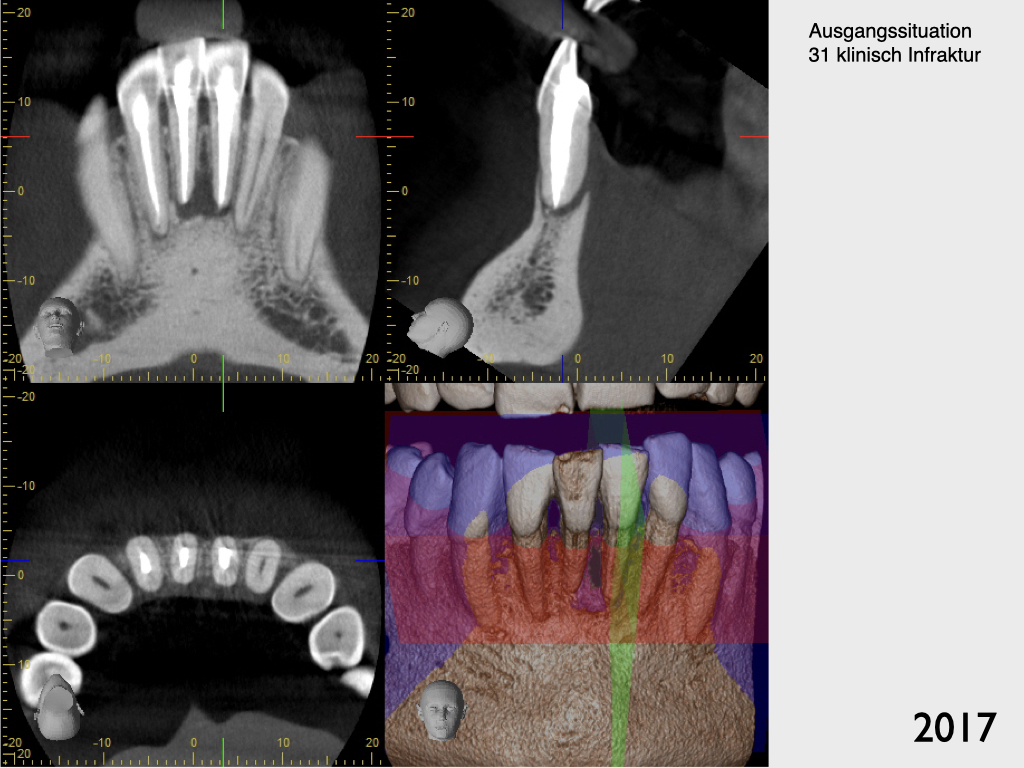

Frontzahntrauma